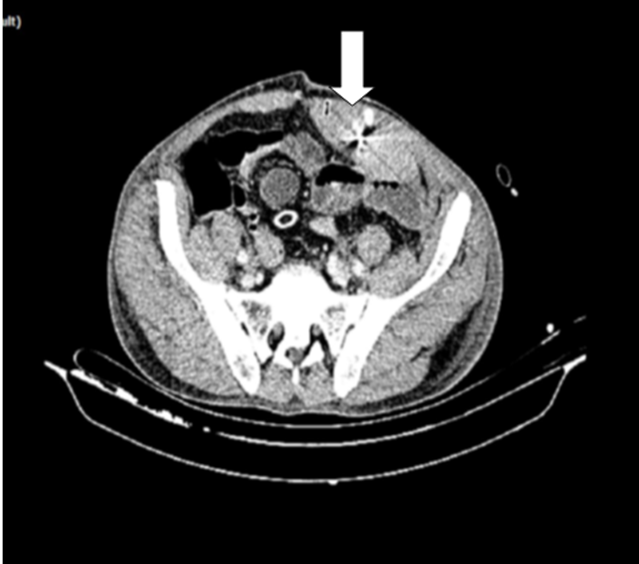

Initially, the patient’s stable condition warranted observation in the emergency department. However, during monitoring, the patient developed tachycardia. Repeat blood tests revealed a hemoglobin drop to

10.9 g/dL and hematocrit to 31.8%. Follow-up tomography showed a hematoma in the left rectus sheath with evidence of intra-abdominal bleeding (Figure 2). As the patient’s condition worsened, including hypotension, an urgent exploratory laparotomy was performed.

Figure 2: Left Rectus sheath hematoma leaking to intrabdominal on Abdominal Pelvic Computed Tomography.